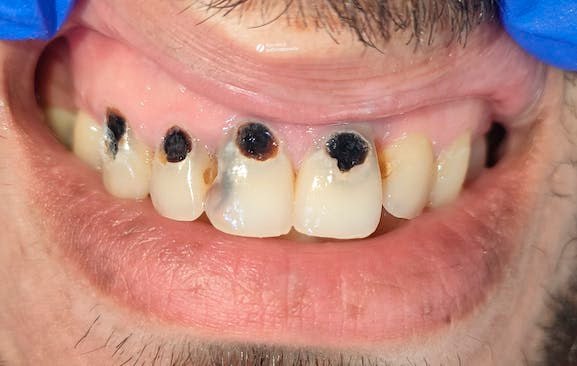

Наглядный пример вылеченного цервикального кариеса - кариес, локализующийся вблизи шейки зуба на границе с десной:

1 мар. 2026 г.

1.5k 30 11